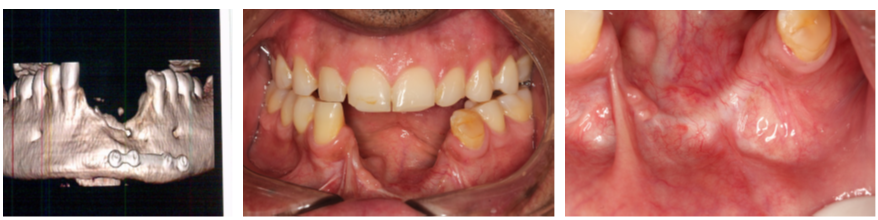

Este caso clínico limítrofe e contempla a reabilitação de um paciente que sofreu um acidente. O trauma resultou na perda do osso, lábios e gengiva inserida e mucosa com bastante necrose dos tecidos, visto que ficou o paciente precisou ficar na UTI por cinco dias e só depois disso recebeu os cuidados odontológicos.

A cirurgia de reconstrução óssea estava contraindicada devido à qualidade ruim dos tecidos moles. Por conta disso, foi planejada uma cirurgia guiada para evitar o descolamento do tecido mole que fatalmente teria muita dificuldade para ter uma reparação satisfatória.

A escolha foi pelo implante Cone Morse Maestro, pois o osso era muito cortical e a macrogeometria do implante Maestro permite a colocação com um torque menor.